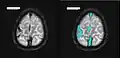

- Bildgebung bei zerebralen Thrombosen (zum Vergrößern Bilder anklicken)

-

-